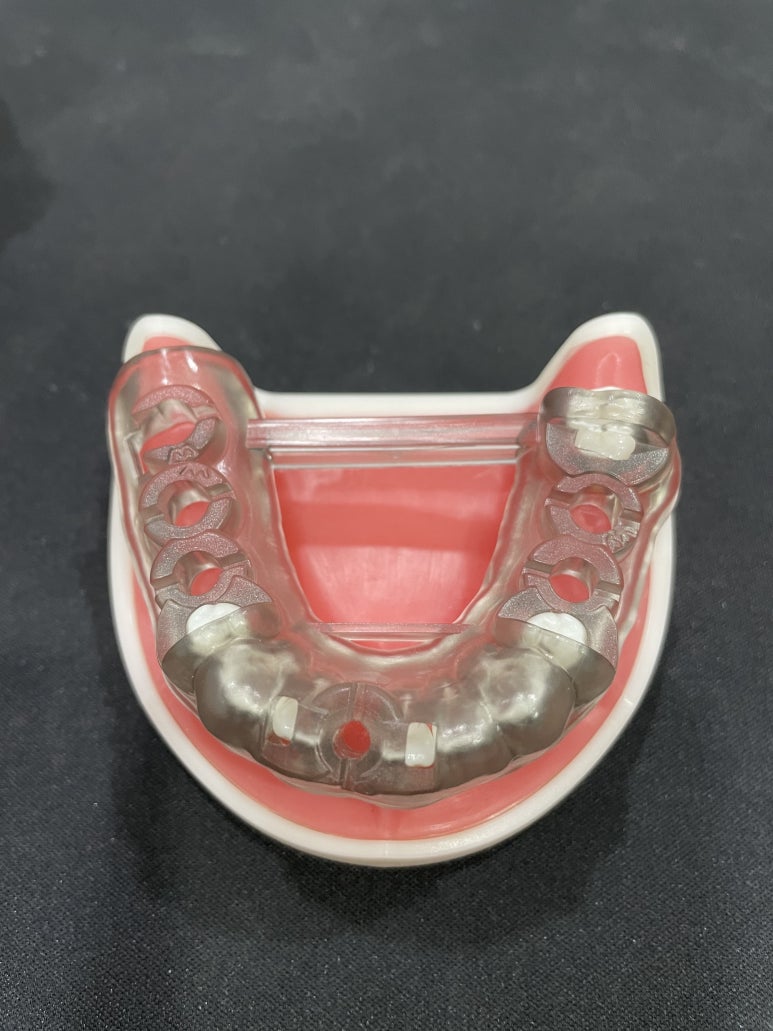

네비게이션 임플란트 수술을 위한 원가이드 샘플

환자분의 구강 및 골격의 구조 등을 면밀하게 파악해 환자분께 딱 맞는 가이드를 제작해야 하는데

이 제작비용이 추가되기 때문에 일반 임플란트보다 조금 더 비싼 것입니다.